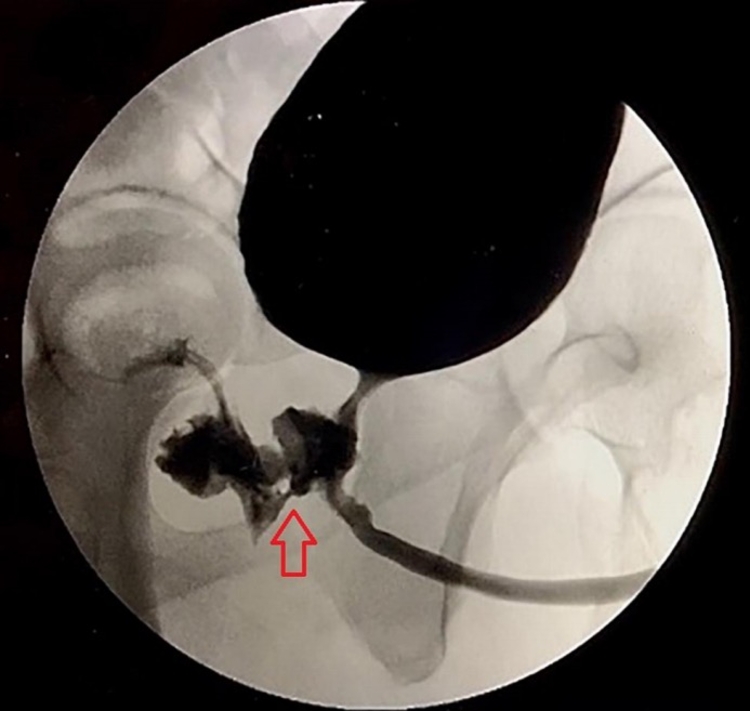

Após diversos exames, imagens revelaram a presença de uma fístula na região do reto e do aparelho urinário. O caso foi relatado por médicos no artigo "Um Curioso Caso de Ejaculação Anal". Ele foi tratado com antibióticos e submetido a uma pequena cirurgia para corrigir a região com a fístula.

Após investigação das causas da condição, que nunca havia sido documentada na literatura, os médicos descobriram que o paciente passou três semanas em coma após uma overdose de cocaína e fenciclidina, dois anos antes do ocorrido. Os médicos concluíram que uma sonda de Foleye, introduzida na região da uretra, pelo tempo prolongado que passou internado, pode ter causado a fístula na região.